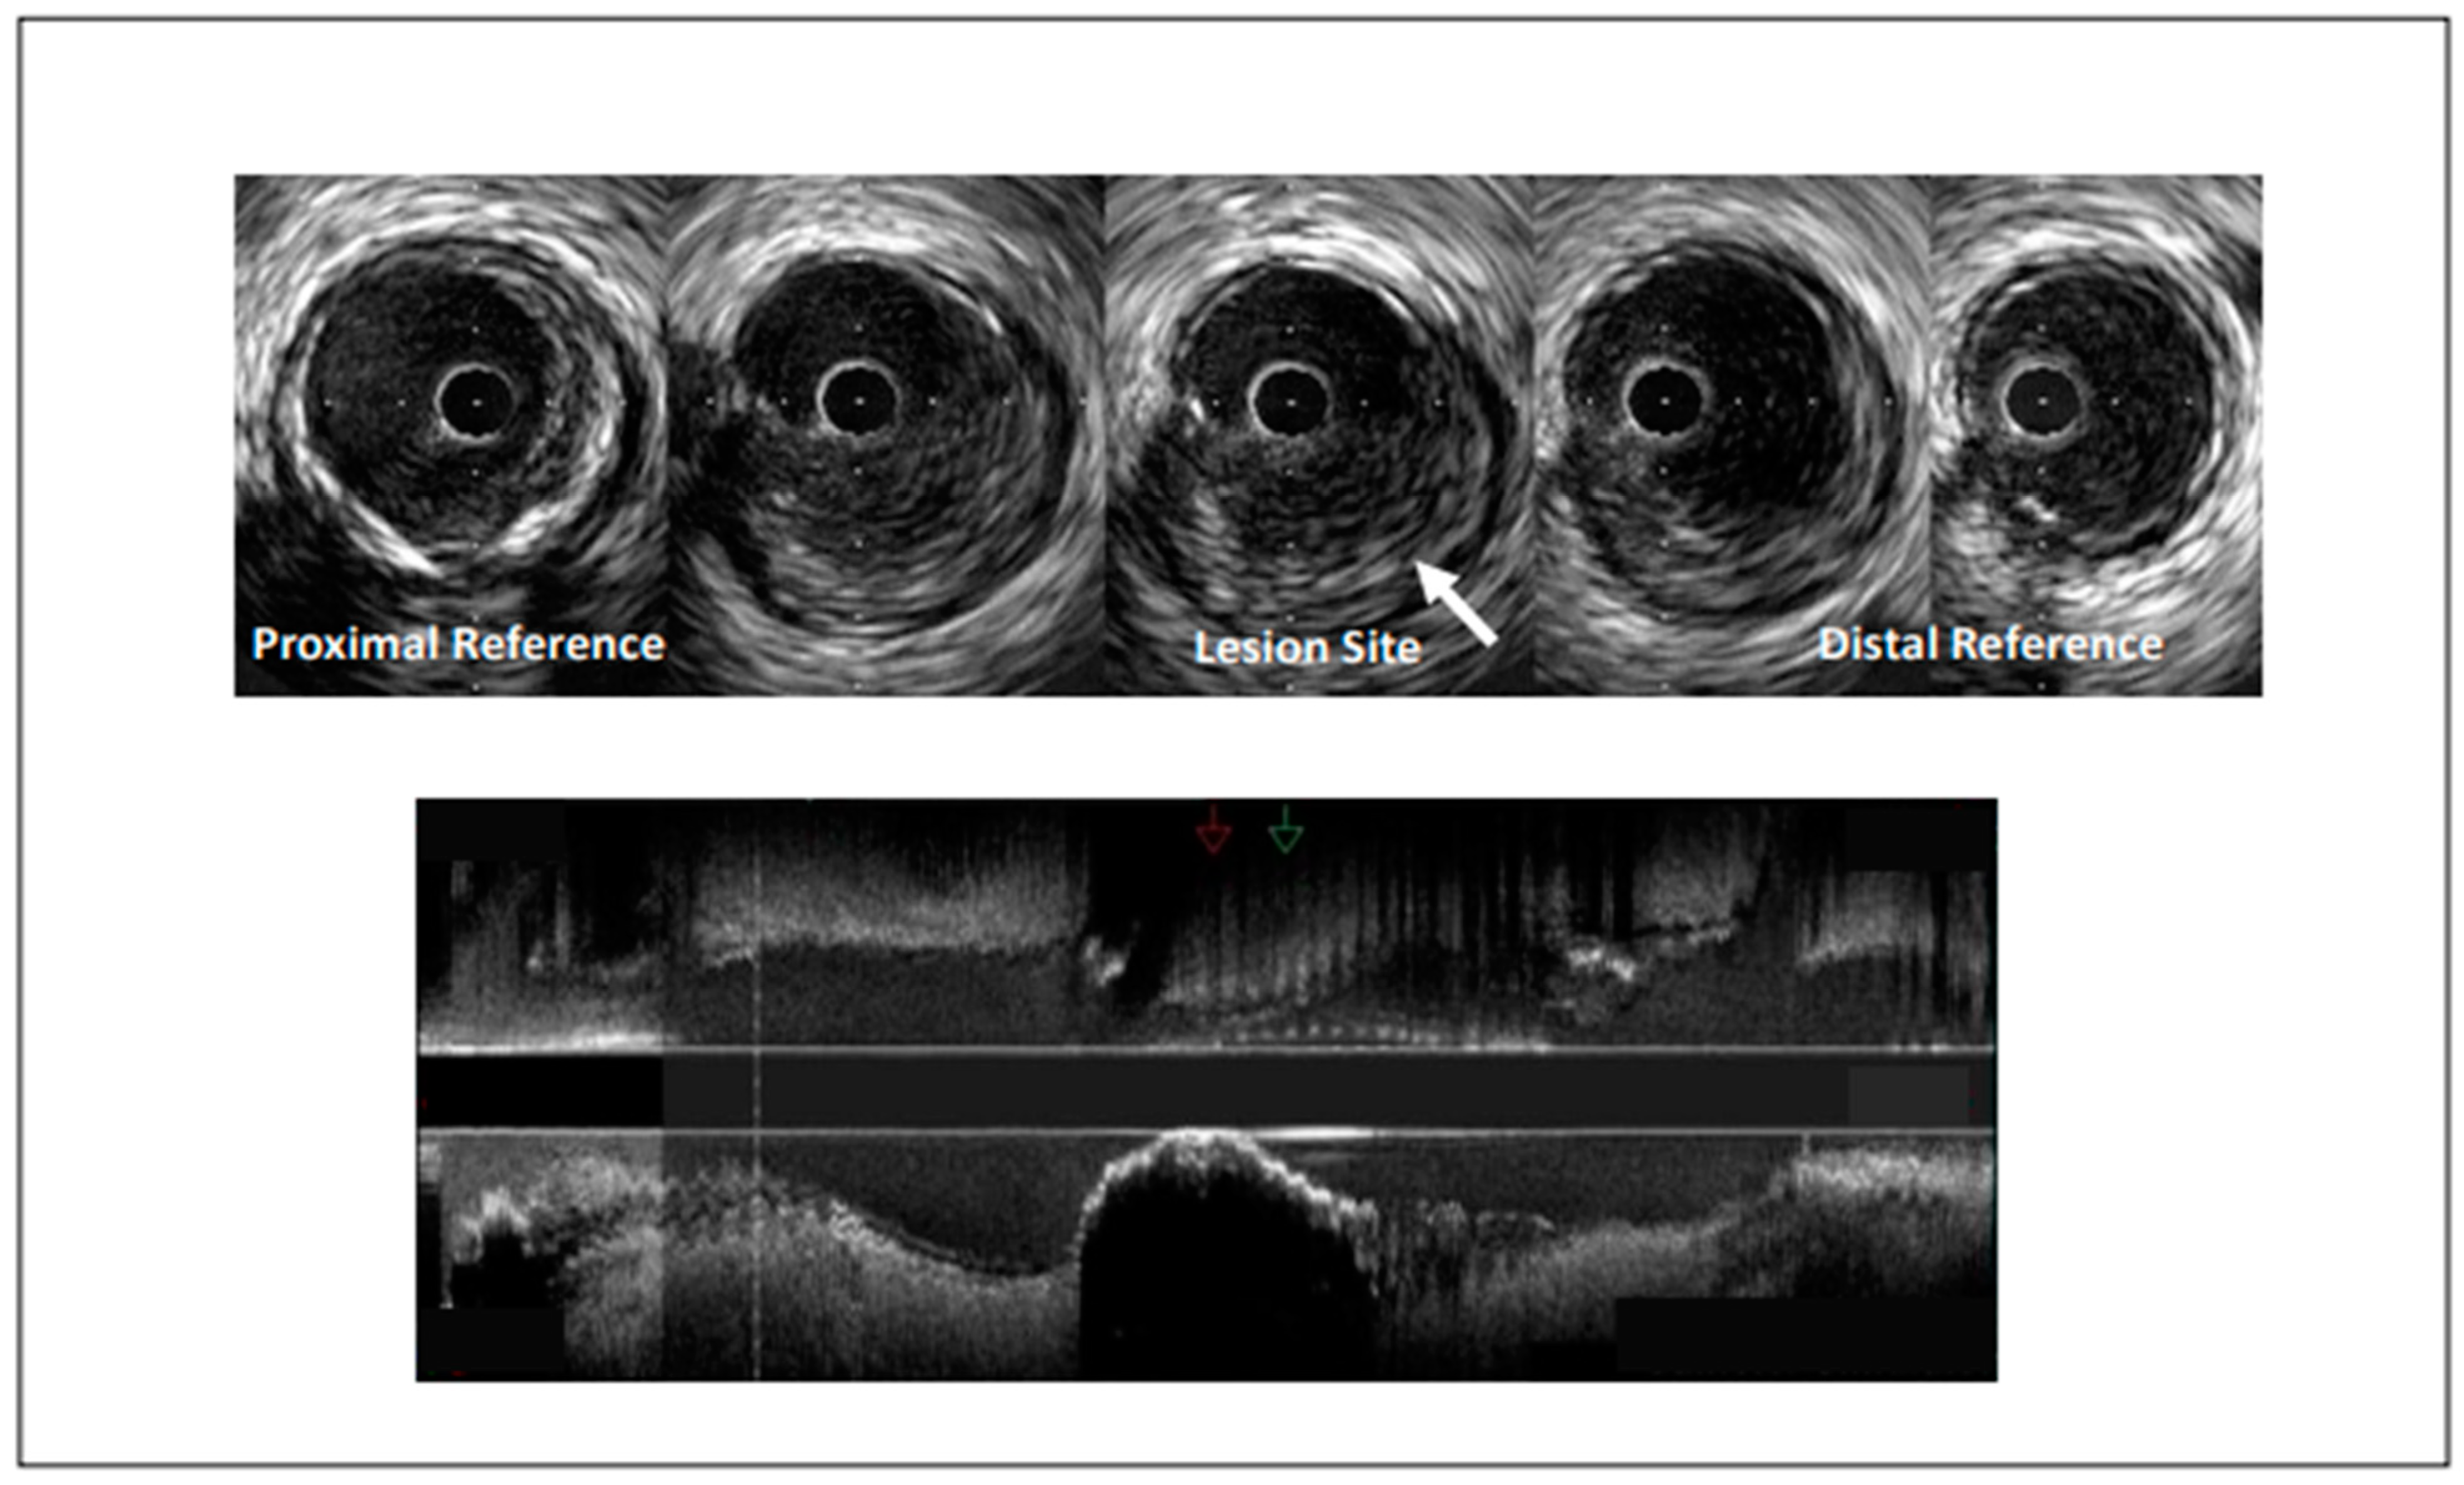

Figure 1.

Intravascular ultrasound demonstrating coronary artery stenosis most likely due to plaque erosion.